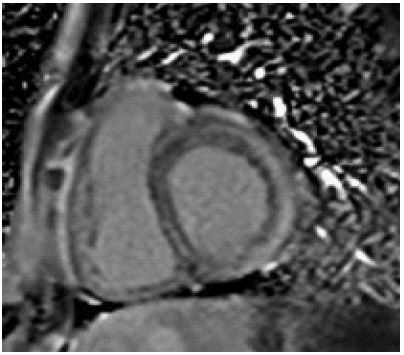

A 33-year-old female with no prior comorbidities presented with a seven-day history of high-grade fever, chills, rigors, dyspnea, and cough with borderline blood pressure requiring inotropes. Preliminary evaluation with ECG revealed sinus tachycardia and a 2D echo revealed global LV hypokinesia and severe Left ventricular dysfunction with LVEF of 30%. Initial laboratory investigations revealed elevated troponin with elevated NT-Pro-BNP suggestive of myocardial injury and acute heart failure, anemia (Hb: 9 g/dL), and elevated TSH (7.8 mIU/L), and mild renal dysfunction. The patient was admitted to the Intensive Care Unit and was treated for Heart Failure. A cardiac MRI was done, and it showed significant mid-myocardial Late Gadolinium Enhancement (LGE) in the LV free wall, sparing the endocardium and epicardium. While mid-myocardial LGE is commonly associated with myocarditis, it can also be seen in other conditions such as sarcoidosis, dilated cardiomyopathy, and Anderson Fabry disease. In this case, the findings were interpreted in conjunction with the clinical presentation, including recent febrile illness, elevated troponin, and rapid LV dysfunction. The imaging met the revised Lake Louise Criteria, supporting a diagnosis of probable myocarditis (Figures 1-3). Patient was started on IV Methylprednisolone 1 g daily for three days and then started on Oral prednisolone 1 mg/kg/day. Four days into her illness, she experienced two syncopal episodes and was found to have bradycardia with a heart rate of 30/min. An ECG revealed a complete heart block (Figure 4) with a wide-complex escape rhythm, and rising troponin levels indicated myocardial injury. A transvenous temporary pacemaker was placed, stabilizing her initially. A formal Transthoracic Echocardiogram (TTE) was performed after temporary pacemaker placement, which revealed the same moderate to severe LV dysfunction and no additional complications. Sarcoidosis was considered due to mildly elevated ACE levels (61 U/L), but further testing, including CT chest, EBUS, and node biopsy, was not feasible due to the patient’s rapid deterioration. Giant cell myocarditis, though rare in young patients, was also considered, given the aggressive course and refractory ventricular arrhythmias. A comprehensive evaluation could not be conducted due to the rapid progression of the disease. However, viral myocarditis remained the most likely etiology based on clinical presentation, negative H1N1 swab, and absence of autoimmune markers (ANA: 1:40, dsDNA < 30 IU/mL) (Table 1). After TPI, she developed slow ventricular tachycardia (130/min) (Figure 5), which persisted despite multiple attempts at overdrive pacing. Amiodarone was initiated (150 mg IV bolus, followed by 1 mg/min for 6 hours, then 0.5 mg/min for 18 hours), but VT remained refractory. Lidocaine (1.5 mg/kg IV bolus, followed by 1 mg/min infusion) was added, but the arrhythmia remained refractory. Overdrive pacing was attempted but was discontinued after the onset of Polymorphic Ventricular Tachycardia (PMVT). Given the fulminant nature of myocarditis, catheter ablation was not attempted, as the arrhythmogenic substrate was likely diffuse rather than focal, reducing the likelihood of procedural success. The patient continued to deteriorate into refractory cardiogenic shock despite maximal inotropic and antiarrhythmic therapy. She experienced cardiac arrest and could not be resuscitated. Referral for mechanical circulatory support (ECMO) was considered, but stabilization for transfer was not possible given the rapid decline. Post-mortem biopsy was not performed due to lack of consent.

Figure 1: Short axis phase contrast T1 sequence shows mid myocardial late gadolinium enhancement along the left ventricular free wall with sparing of endo & epicardium.